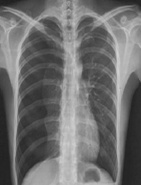

| 病史:男性,65岁,突感胸闷气促1小时。诊断: |

| ○ 右侧气胸 | |

| ○ 右侧大叶性肺炎 | |

| ○ 右侧胸腔积液 | |

| ○ 肺结核 | |

| ○ 右侧肺癌 |